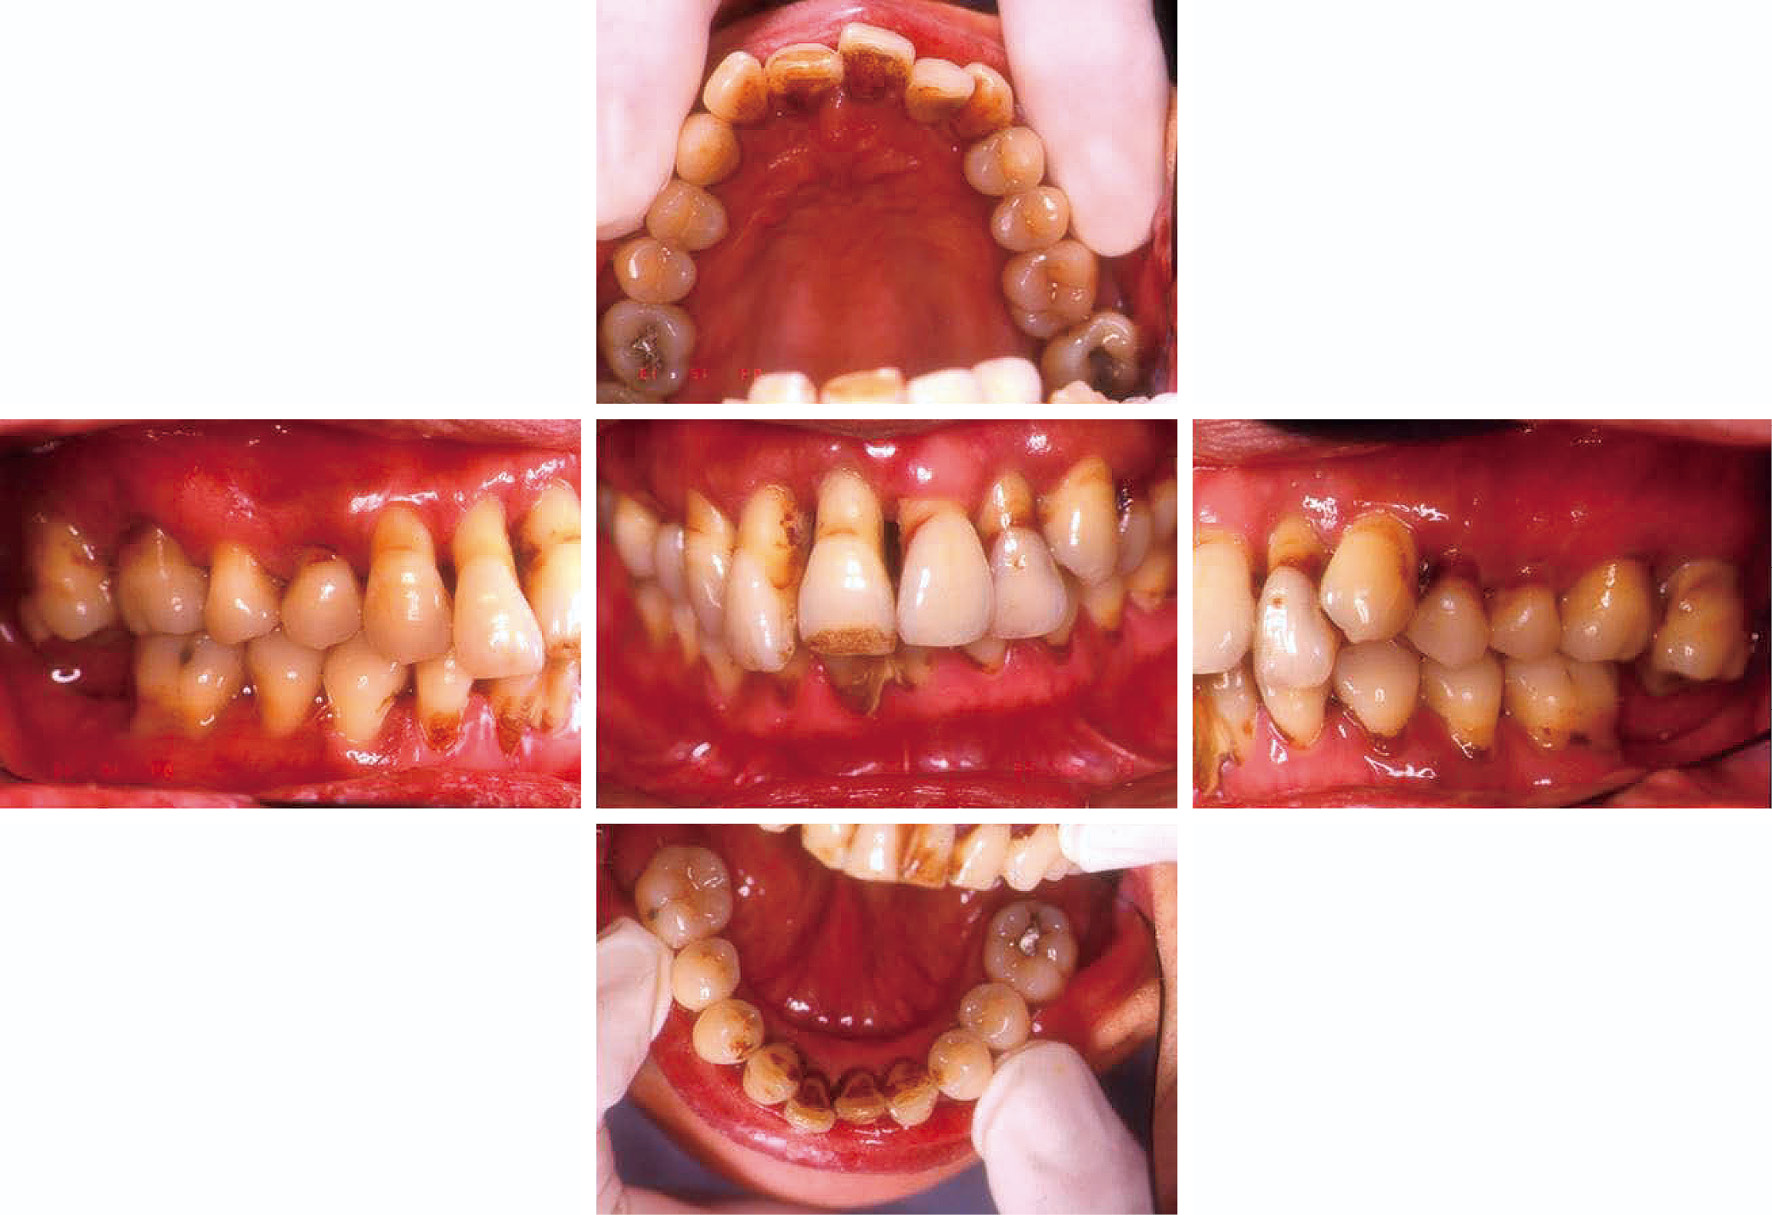

b) 治療方針と治療計画広汎型重度慢性歯周炎で喫煙関連性歯周炎でもある(図2,図3)。市場でご主人と天ぷらを揚げて販売している。仕事が多忙で,毎日疲労感が強く,睡眠も十分に取れない。重大な悩み事を持っている(内容不明)。細身体で,明らかにタバコ臭がある。歯周組織検査後,病状の説明を行い,治療計画を説明した。その際,希望があれば「禁煙指導」をする旨伝えたが,受諾はなかった。当時(平成6年)は現在ほど禁煙キャンペーンに熱心ではなかったことも災いしている。しかし,歯肉退縮,年齢42歳でかなりやせ型,タバコ臭と喫煙の悪影響がみられ,深いポケット残存部へのフラップ手術も計画しづらく,また再発の危険性も高いため,プラークコントロールレベルの改善に加えて禁煙達成を歯周外科手術実施の条件として計画を立てた。患者から得られた情報は歯周組織所見(図2)として歯根露出(歯肉退縮),歯の挺出,歯の着色,歯石沈着等であった。歯肉に発赤・腫脹の炎症所見が認められる。同様に,エックス線写真(図3)より,全顎的に高度な歯槽骨吸収がみられ,37および47は既に欠損し,17,16,12,11,22,24,25,26,27,31,41,42はほぼ根尖に至る骨吸収像,上下大臼歯はすべて根分岐部病変に罹患していることが分かった。

初診時(42歳,女性)の口腔内写真。